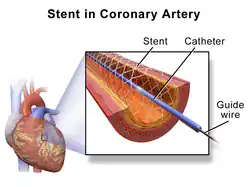

Percutaneous coronary intervention (PCI) is a minimally invasive non-surgical procedure used to treat narrowing of the coronary arteries of the heart found in coronary artery disease.[2] The procedure is used to place and deploy coronary stents, a permanent wire-meshed tube, to open narrowed coronary arteries. PCI is considered 'non-surgical' as it uses a small hole in a peripheral artery (leg/arm) to gain access to the arterial system; an equivalent surgical procedure would involve the opening of the chest wall to gain access to the heart area. The term 'coronary angioplasty with stent' is synonymous with PCI. The procedure visualises the blood vessels via fluoroscopic imaging and contrast dyes. PCI is performed by an interventional cardiologists in a catheterization laboratory setting.[3]

PCI consists of preparation of the skin area to be accessed (groin or arm), by shaving and swabbing the area with a bacteriostatic agent, usually a chlorhexidine based product. An introducer needle is inserted into the target artery. Once the access is gained, a "sheath introducer" is inserted to keep the artery open. This procedure is termed percutaneous access. As of 2023, catheter systems used in PCI procedures are often fully integrated medical devices. They are usually referred to as "over the wire" or OTW catheters.[19] Typically having two lumen paths (a cavity within any tubular structure), the larger one for the navigating highly flexible guidewire and the smaller one for inflating and deflating the balloon or balloon/catheter assembly. The guidewire lumen extends the total length of the catheter. A balloon-stent is often part of the assembled device, other features may also be part of the medical device design depending on the nature of the procedure.[20]

The interventional cardiologist uses the entry point created during the percutaneous access step, to introduce the catheter system and guides it to the occluded area of the coronary artery being treated, using fluoroscopy and radiopaque dyes as an imaging tool. The device and its balloon/stent components can be inflated to open the stenotic diseased artery area. When a stent is used, the stent tube mesh is initially collapsed onto the balloon component of the catheter. In this collapsed state, it is small enough to be passed though relatively narrow peripheral arteries and then inflated by the underlying balloon and pressed firmly against the diseased coronary artery wall. It is expanded by pressure introduced by injecting physiological saline into the device through the lumen of the still attached catheter. Inflation time and pressure used are recorded during this placement procedure. After the balloon inflation/deflation or the deposition of the stent, the placement device/deflated balloon are removed leaving the stent in place.[21][22]